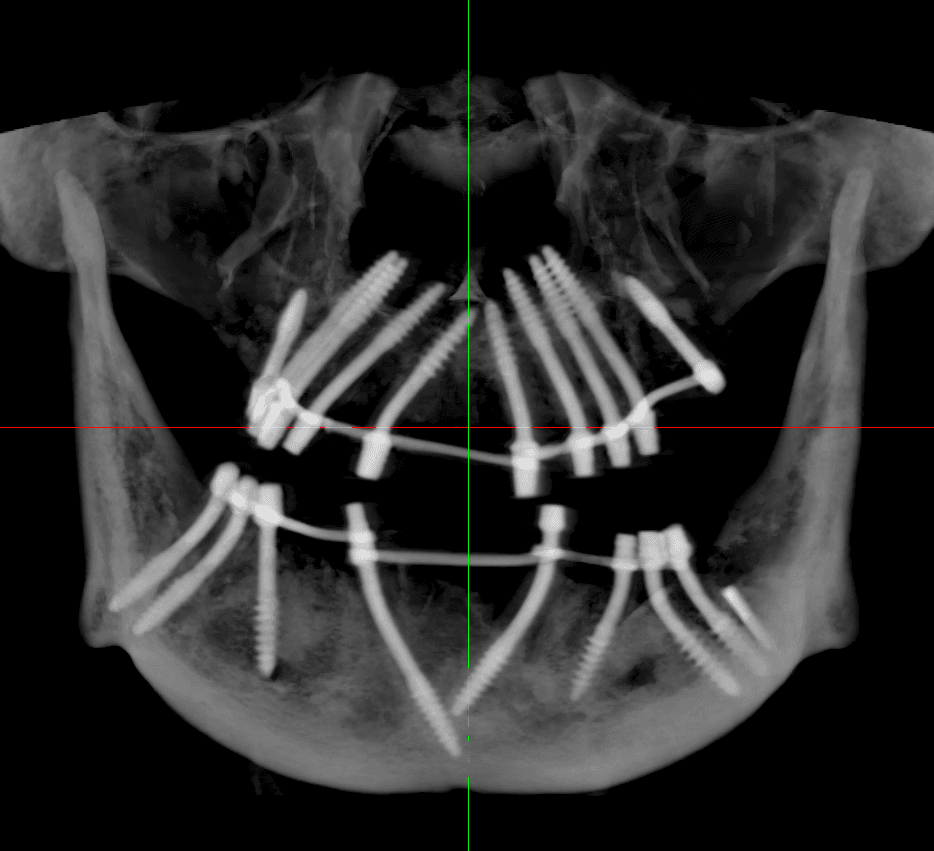

Bi-cortical Engagement

Master the art of bicortical engagement for unmatched implant stability. Learn advanced corticobasal techniques, including nerve bypass, ensuring immediate loading and longterm success.

Direct exposure to 500+ strategic corticobasal implants

Live training in bicortical planning, nerve bypass, sinus avoidance

Nerve bypass is an important technique to rehabilitate the posterior mandible without risking inferior alveolar nerve injury. It allows placement of implants in severely resorbed jaws while avoiding neurosensory complications.

Master tricortical engagement for superior implant stability and longevity. Get hands-on experience placing pterygoid implants on live patients and gain key insights on zygomatic implants. Learn advanced corticobasal techniques.